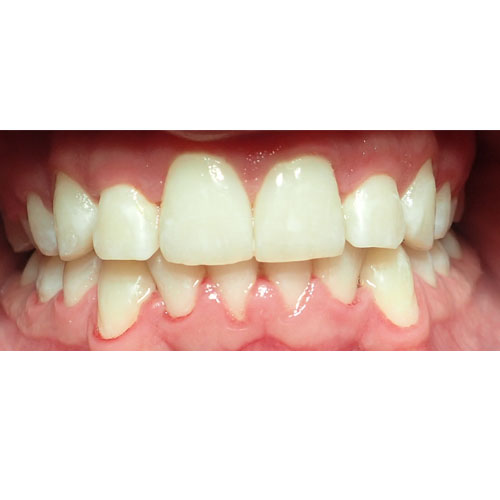

Nasze rezultaty